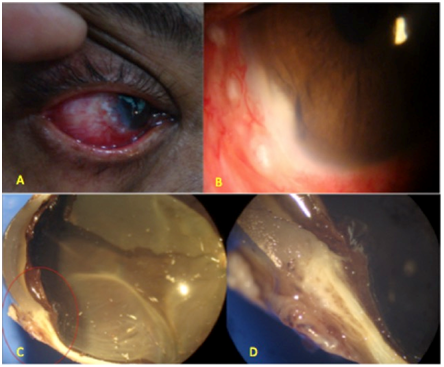

On examination white coloured mass in temporal irido-corneal angle (Figure 1B) which was pre-occluding the iris along with surface changes, was noted (Figure 1A). The unhealthy looking tissue was lisamine green positive.

Figure 1 Torch light (A) & Slit lamp examination B showed a white coloured mass in temporal irido-corneal angle which was pre-occluding the iris along with surface changes. Gross visualization (C & D) after En-block enucleation.

On basis of clinical appearance, UBM and MRI findings diagnoses of Squamous Cell Carcinoma with intraocular and lacrimal tissue spread were made. En-block enucleation with Mitomycin C application (Figure 4C) (Figure 4D) along with lacrimal tissue resection and cryotherapy to vortex veins was done and ball implant was placed. Margins of conjunctiva were resected till it was free of altered cells on frozen section. Histology of enucleated eye Figure 4D showed keratin pearls (Figure 4A) along with atypical undifferentiated cells (Figure 4B) (Figure 4C) and confirmed it to be Squamous Cell Carcinoma of Grade-II involving Conjunctiva, Limbus, Anterior Chamber, Ciliary Body and Retina (With localized exudative RD) with no involvement of Lacrimal Gland.